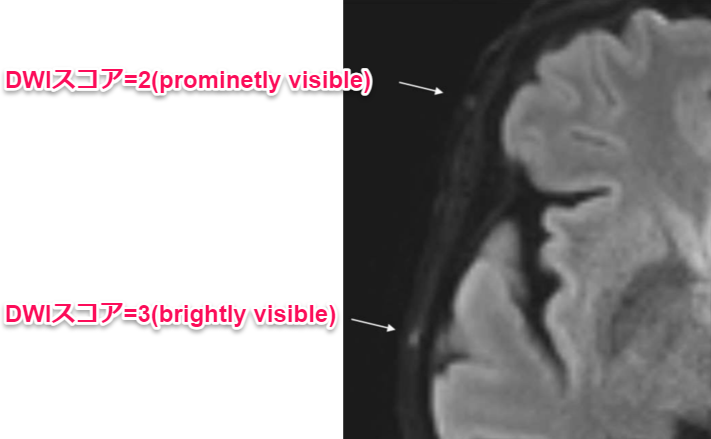

巨細胞性動脈炎の拡散強調像での簡便な診断方法に関する研究

(コメント)

確かに当院のGCA患者で見てみてもDWIで高信号があり、病理結果とも一致している印象であった。側頭動脈ができない or 結果が早く知りたい状況だが、超音波検査を当てられないシチュエーションでは参考になる所見と思われる。